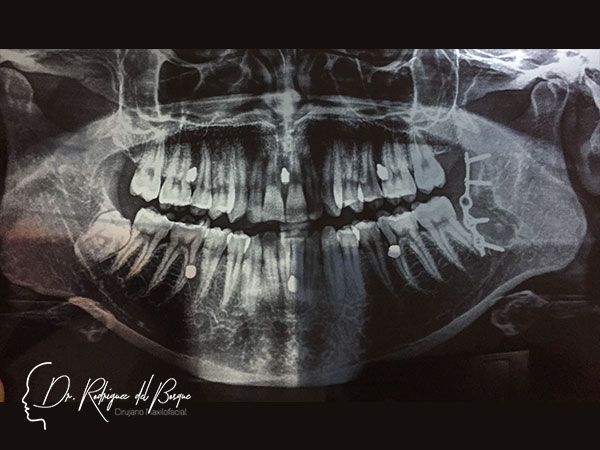

Implantes Dentales

Los implantes dentales están indicados cuando se ha perdido un organo dental, es una excelente opcion de tratamiento siempre y cuando se cumplan con los requisitos biológicos y protesicos para que un paciente Sea candidato.